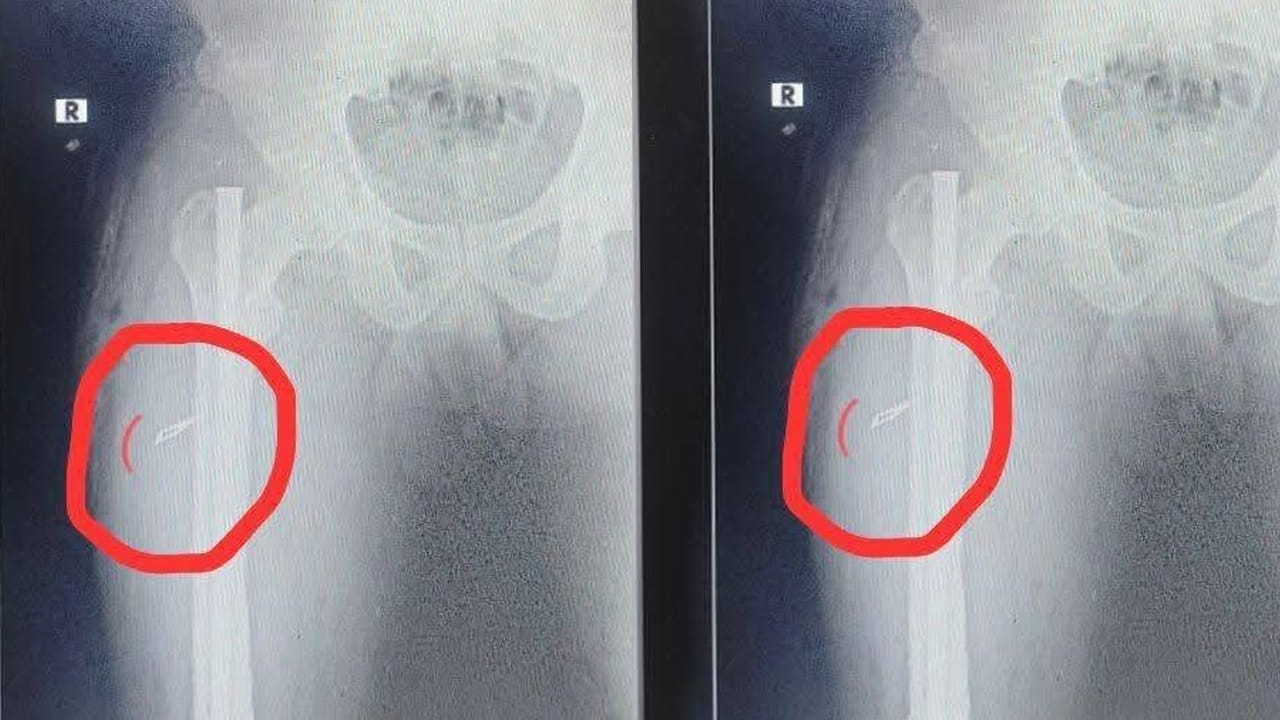

కాకినాడ జిల్లా తుని మండలం ఎస్.అన్నవరం పంచాయితీ రామకృష్ణ నగరంకు చెందిన చిన్న(25) అనే వ్యక్తి ఏడాదిన్నర క్రితం కాలుకు గాయం తగలడంతో వైజాగ్లో గాయంకు ఆపరేషన్ చేయించుకున్నాడు. అప్పట్లో కాలికి బలంగా దెబ్బతగలడంతో లోపలి భాగంలో రాడ్ అమర్చి ఆపరేషన్ చేశారు. ఏడాదిన్నర గడిచిన తర్వాత వెలుపల ఉన్న ఒక బోల్ట్ తీస్తే త్వరగా సెట్ అవుతుందని చెప్పడంతో.. కాలులో రాడ్కు ఉన్న బోల్ట్ తీయించుకునేందుకు తుని గవర్నమెంట్ హాస్పిటల్కి వెళ్లాడు. అక్కడ సిబ్బంది ఆపరేషన్ చేసి రాడ్ బోల్ట్ వెలపలకు తీశారు. కానీ కాలులో మాత్రం సిజెరియన్ బ్లేడు ఒక్కటి ఉంచి యధావిధిగా కుట్లు వేయడంతో.. ఆ విషయాన్ని స్కానింగ్లో గుర్తించాడు సదరు బాధితుడు.